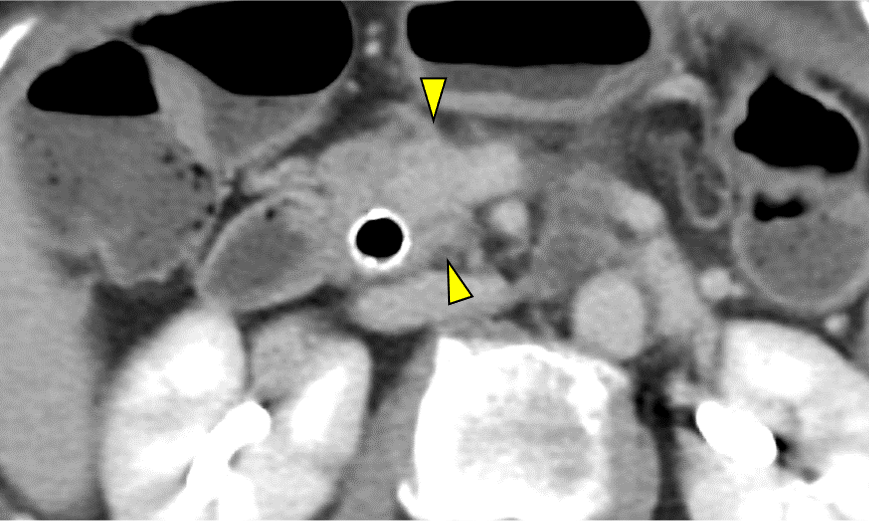

図5.造影CT 膵実質相 Axial像 40keV

40keVの仮想単色X線画像では、70keVの画像と比較して膵癌病変(矢頭)と正常膵実質(矢印)の境界はより明瞭に描出されている。